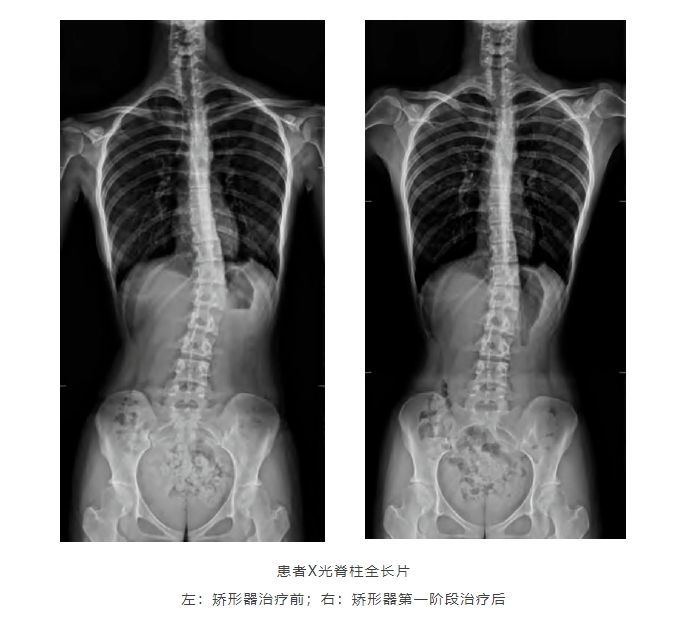

家长如何在家自行观察孩子是否有脊柱侧弯?